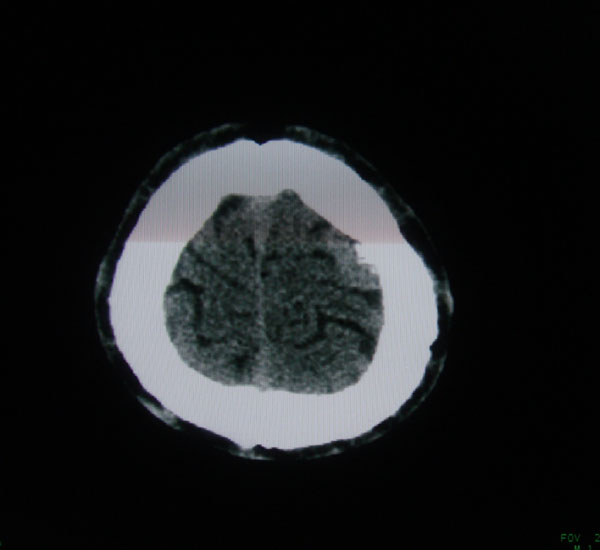

以下是引用拾荒者在2008-6-7 13:05:00的发言:[br]左侧顶骨局限性骨质缺损,边缘锐利,无硬化边,周围软组织轻度肿胀,无明显软组织肿块及骨膜反应,考虑嗜酸性肉芽肿可能。